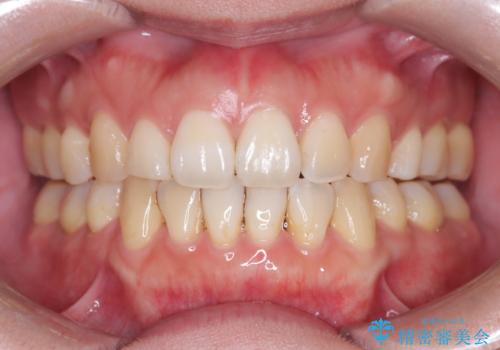

前歯の突出を防ぎながらガタつきを解消。上下左右4番抜歯による審美ワイヤー矯正